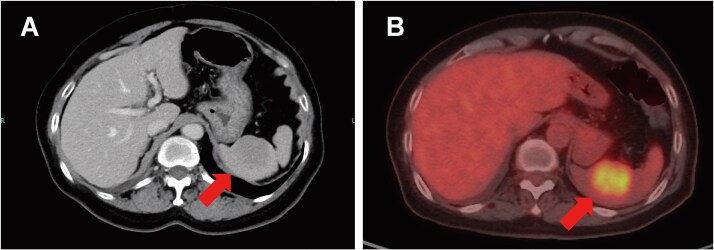

Splenic metastasis is uncommon, and truly isolated splenic metastasis (ISM) from breast cancer is a clinical rarity. Contemporary autopsy series reports splenic involvement in <1% of breast cancer-related deaths, and fewer than 15 well-documented ISM cases have been published. We report a 71-year-old woman presenting with a right-breast mass, regional lymphadenopathy, and a solitary splenic lesion detected on staging computed tomography (CT) and positron emission tomography-CT. Biopsy confirmed hormone receptor-negative, HER2-positive invasive ductal carcinoma. Six cycles of docetaxel, trastuzumab, and pertuzumab led to a 59% reduction in the primary tumour and complete radiological resolution of the splenic lesion. The patient remains progression-free 22 months after initiating therapy, maintained on trastuzumab and pertuzumab. Although extremely rare, ISM can present as the initial manifestation of de novo metastatic breast cancer. Awareness of this possibility may facilitate early systemic therapy and obviate the need for diagnostic splenectomy.